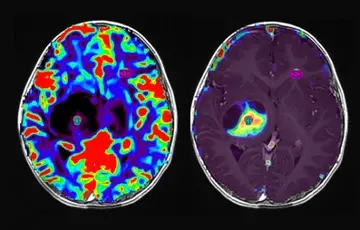

OLEA SPHERE® IST EINE AUTOMATISIERTE, MULTIMODALE UND HERSTELLERNEUTRALE NACHBEARBEITUNGSSOFTWARE FÜR MRT- UND CT-SCANNER. SPEZIELLE ALGORITHMEN BERECHNEN MULTIPARAMETRISCHE KARTEN UND WERTE. DAMIT KANN DIE PRODUKTIVITÄT GESTEIGERT, DIE DIAGNOSEQUALITÄT ERHÖHT UND DER GESAMTPROZESS OPTIMIERT WERDEN.

FORTSCHRITTLICHE MR-TECHNIKEN ERLAUBEN EINE VERBESSERTE DIAGNOSTIK BEI FUNKTIONSSTÖRUNGEN DES ZENTRALNERVENSYSTEMS UND EINER VIELZAHL VON ONKOLOGISCHEN ERKRANKUNGEN. DURCH SOLCHE MODERNEN VERFAHREN WERDEN VERÄNDERUNGEN AUF ZELLULÄRER, METABOLISCHER UND FUNKTIONELLER EBENE FRÜHZEITIG SICHTBAR UND ERMÖGLICHEN EINE DEM KRANKHEITSBILD ZUGESCHNITTENE THERAPIE.

UNSERE APPLIKATIONEN FÜR DIE NEUROLOGIE LIEFERN SCHNELLE CT- UND MRT-BILDER DES GEHIRNS ZUR UNTERSCHEIDUNG VON GUT- UND BÖSARTIGEN ERKRANKUNGEN SOWIE EINE BEURTEILUNG AUF DAS THERAPEUTISCHE ANSPRECHEN UND DES KRANKHEITSVERLAUFS.